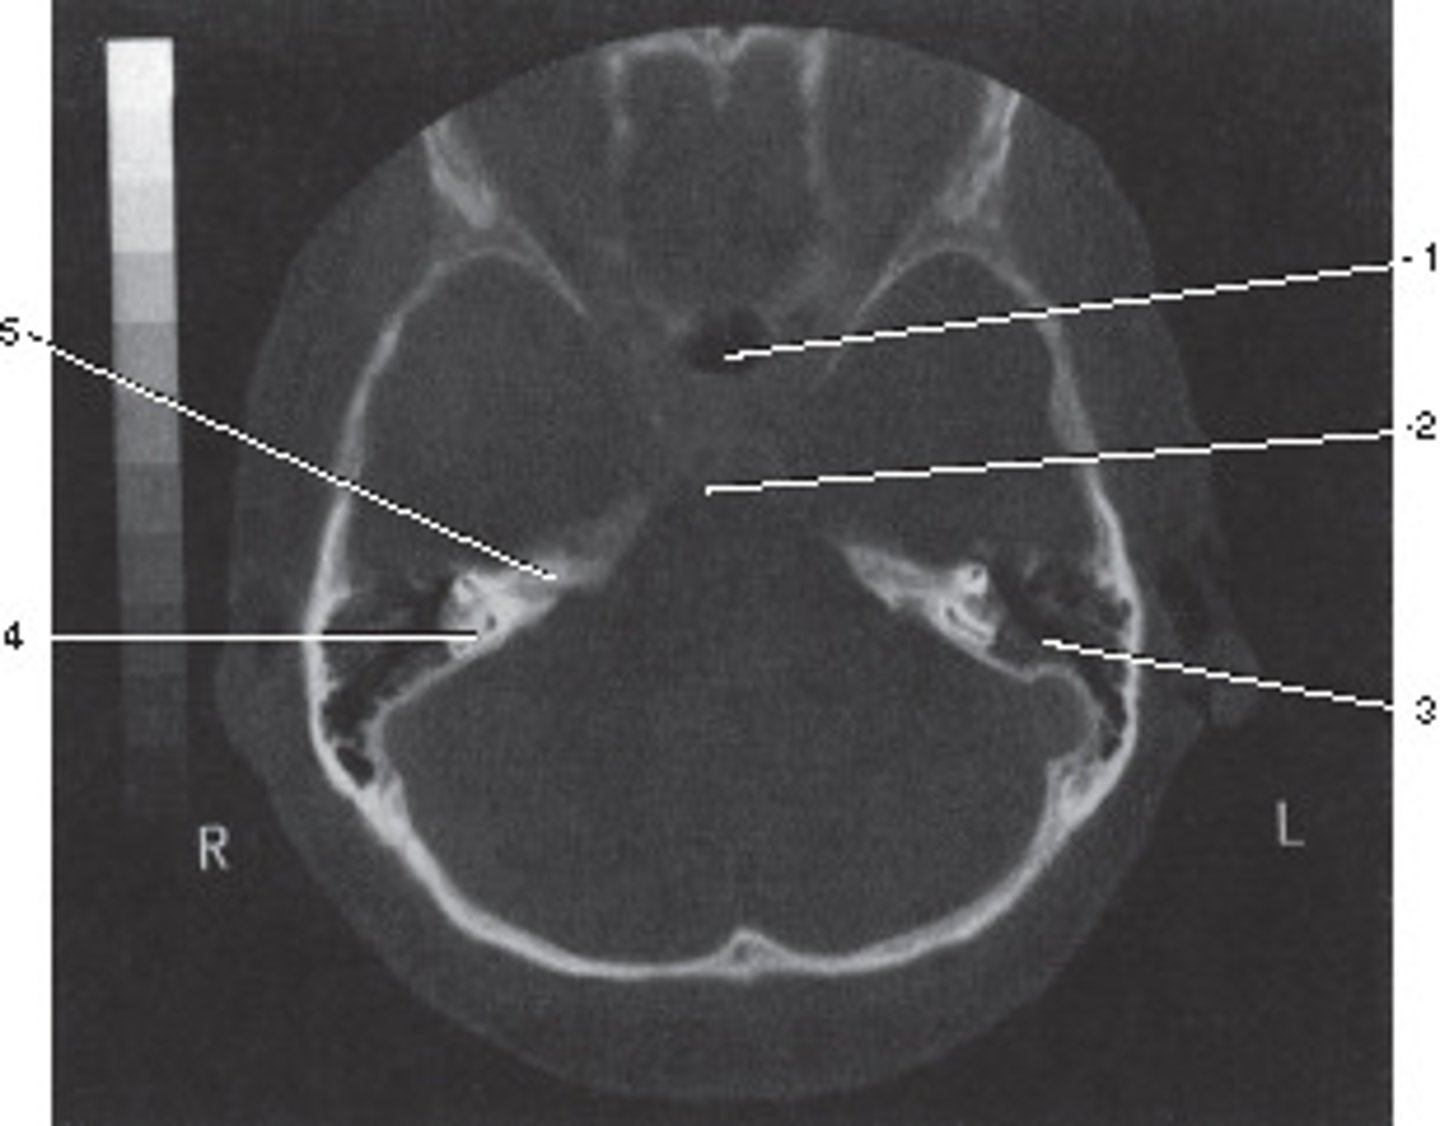

Soft Tissue

What algorithm was used in this image?

<p>What algorithm was used in this image?</p>

14

New cards